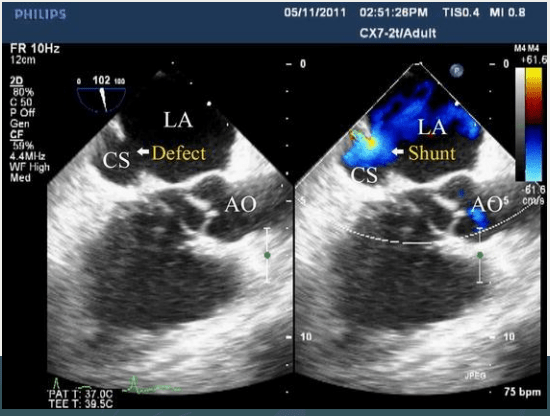

Identify type of ASD

Coronary Sinus ASD

Name these 4 parameters that fulfil the requirement for ASD closure.

Right heart enlargement

PVR <1/3 SVR

PASP <50% systemic

Shunt large enough to cause sequelae (Qp/Qs >/= 1.5:1)